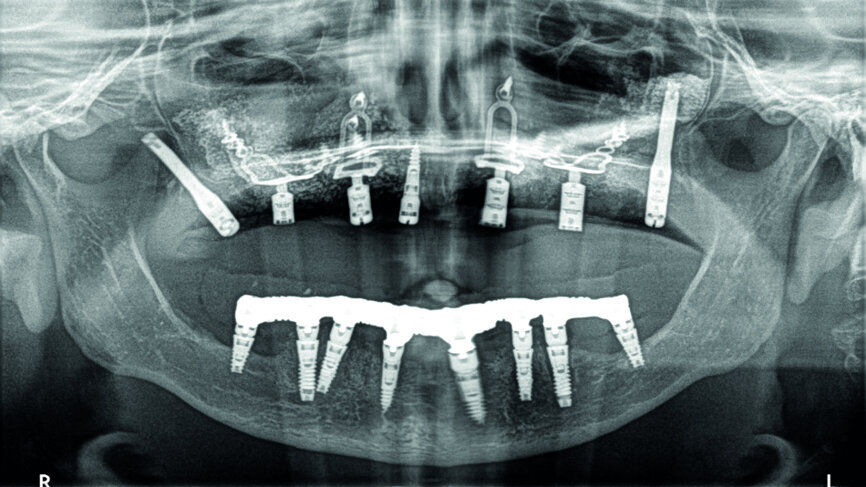

Cas 1f : Contrôle radiologique

Cas 2d : contrôle radiologique